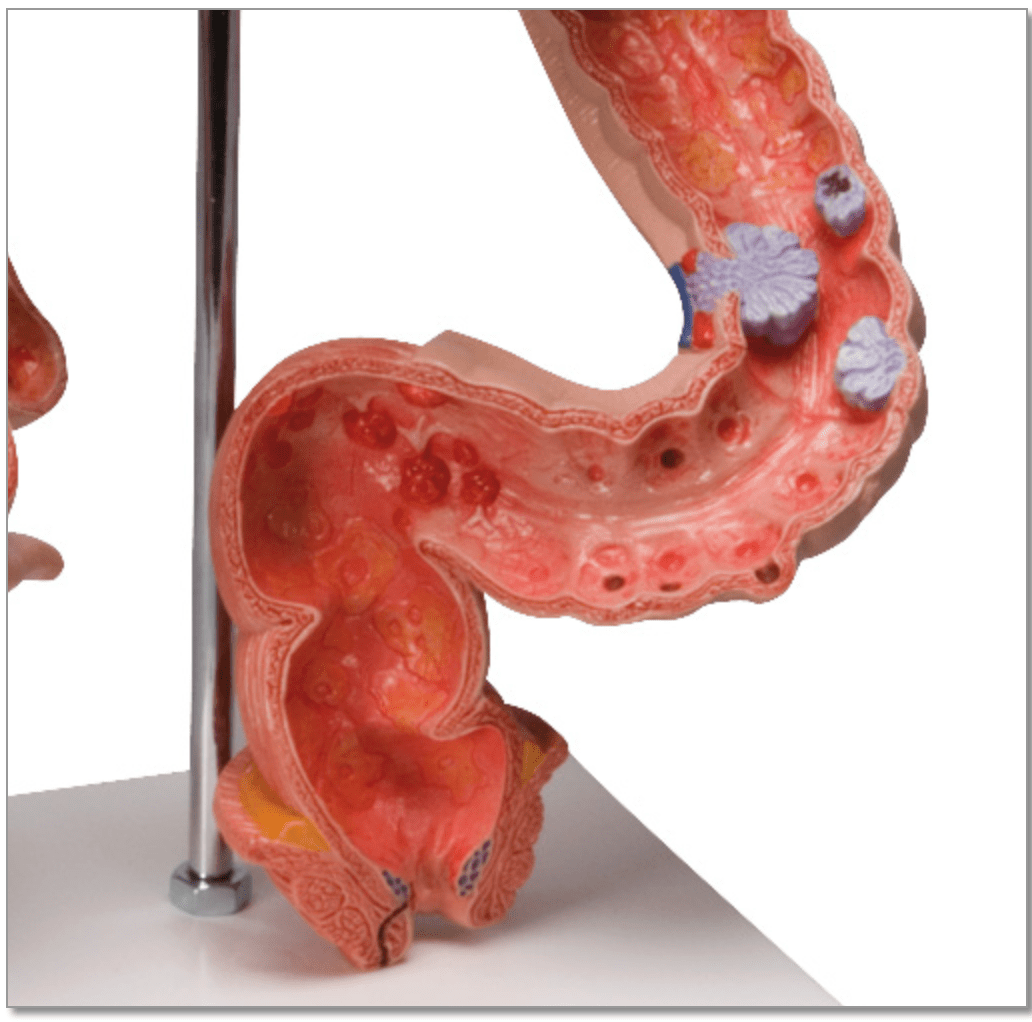

Anatomical models

Selling anatomical models is the mainstay of eAnatomi, although we also spend a lot of resources developing our own anatomical materials such as posters. Anatomical models are used for various purposes and can show both defined tissues, organs and organ systems. Are you looking for a simple model of bone tissue or perhaps an advanced torso model based on MRI technology, you can find it all at eanatomi.com.